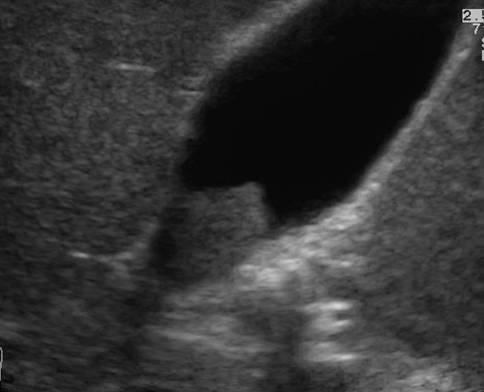

Ung thư túi mật

» Thông tin: Nam giới – 75 tuổi.

» Lâm sàng: Đau mạn sườn phải.